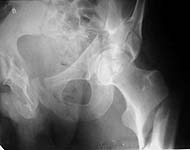

A 45 years old male admitted to us a couple of weeks ago, 5 days after a car crash, with multiple injuries, including severe pelvis and acetabular lesion, and ipsilateral subtrochanteric fracture (see attachment - sorry i put the only view but IMHO all relevant to the question can be seen), and full pattern of fat embolism and ARDS. So the only surgery performed on admission was a pelvic frame with femoral extension, and since the moment he has been ventilated in ICU. He is still not ready to major open surgery for the acetabulum, tomorrow he is sheduled to closed nailing of the humerus and both ulnae.

The question is about the femoral fracture - should it be open and fixed along with acetabulum, or it makes sense to perform less invasive fixation like closed Ender nailing (hello to Bill Burman - i found few rectangular 5x5mm titanium rods), and go for the acetabulum when his condition allows, if needed, with usual osteotomy of the greater trochanter. Or the femoral fracture can help to expose the acetabulum so has to be fixed after it?

The key piece of information missing is what the acetabulum fracture looks like...then you know the incisions required...and can plan from there. This would be project number one. The patient has ramus fractures as well...is the posterior pelvic ring intact? Retrograde nailing of this fracture is a lousy idea. It is subtroch and comminuted. An antegrade nail could be locked into the intact lesser trochanter, but there is not much bone...and I would prefer a cephalomedullary nail. Give us more information

My preference would be to fix both fractures at the same time. Best I can tell from the single view, this guy has a complex acetabular fracture. He's several weeks out. Here in Dallas, we'd use an extensile approach to fix him. I think it goes without saying (but I'll say it anyway) that you need to try to get an anatomic reduction of the acetabulum. I think it's gonna be tough to do that 3 or 4 weeks out from injury.

At the time of the acetabular fx repair, I would fix the femur. He's got a subtrochanteric fracture, but it looks like the lesser troch is intact. You could TRY to use a standard nail with an oblique locking screw - from the greater into the lesser troch - but I think you'd get better stability if you used a nail that had screws going up into the neck. Like a recon nail, or a long gamma nail or long IMHS.